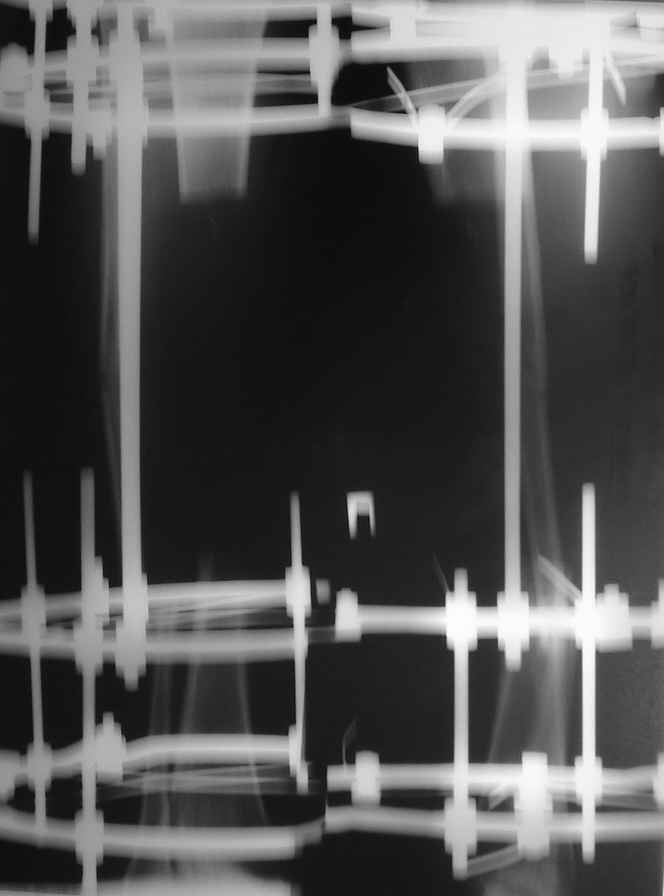

В настоящее время целостность мягких тканей голени полностью восстановлена, кожные лоскуты на мышце розовые фиксированные, раны закрыты на 100%, больной активен, ходит на костылях с дозированной нагрузкой на ногу в аппарате. Планируем выписать его на месяц по месту жительства. И если не получится с Минском, сделаем ему как и планнировали что-то вроде операции Гана-Кодивилла-Геттингтона. Пациент заранее настроен на длительное лечение в аппарате Иллизарова, уже хорошо адаптирован,оптимистичен и пока очень доволен результатами, отмечает значительное улучшение самочувствия. В приложении высылаю фотографии рентгенограм до и после операции.

В приложении рентгенограмма через год после операции.